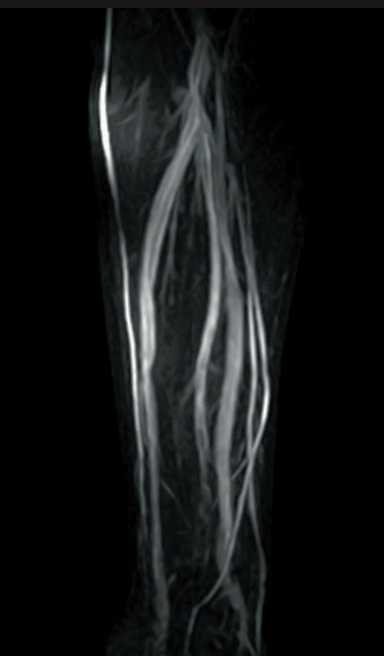

2D-TOF MIP image